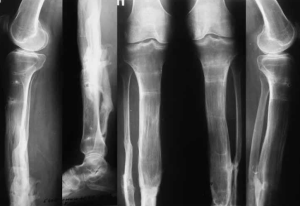

острые травматические повреждения коленного сустава, голени, голеностопного сустава и стопы (переломы, вывихи, разрывы связок) в анамнезе;

наличие гнойно-воспалительных осложнений (остеомиелит, гнойный артрит, флегмона, абсцесс), развившихся в процессе лечения и в течение первого года после лечения;

Таким образом, отобрано 114 пациентов, пролеченных на базе больницы имени Н.В. Соловьева (Ярославль) в различные периоды с 2018 по 2024 гг. Коморбидные патологии выявлены у 93 (81,6 %) пациентов (табл. 1).

Формирование осложнения или его рецидива (табл. 2) определяли при госпитализации пациента в профильный стационар с выполнением всех необходимых клинико-диагностических мероприятий и алгоритмов в рамках действующих протоколов и клинических рекомендаций.